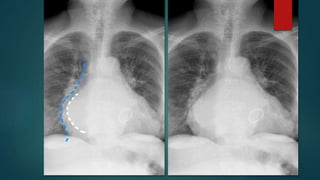

 Splaying of carina.

 Double heart border/

Double density sign

 Signs of a mitral heart:

 Cardiomegaly

 Double right heart border - due to

enlargement of the left atrium.

 Prominent left atrial appendage.

 Severe splaying of the subcarinal

angle (150 degrees) - due to

compression from enlarged left

atrium.

• #8 Stenotomy sutures and prosthetic valve implant are seen. The cardiac shadow is enlarged. A double right heart border is noted. Prominence of pulmonary vasculature in the upper zones which indicates cephalization. Widening of carinal angle >90 degrees aortic knuckle calcification is seen ...Prominence of mid part of left heart border suggesting enlarged left atrial appendage.

• #9 White line enlarged left atrium Atria may be massively enlarged crossing the right atrial shadow k/a Atrial escape